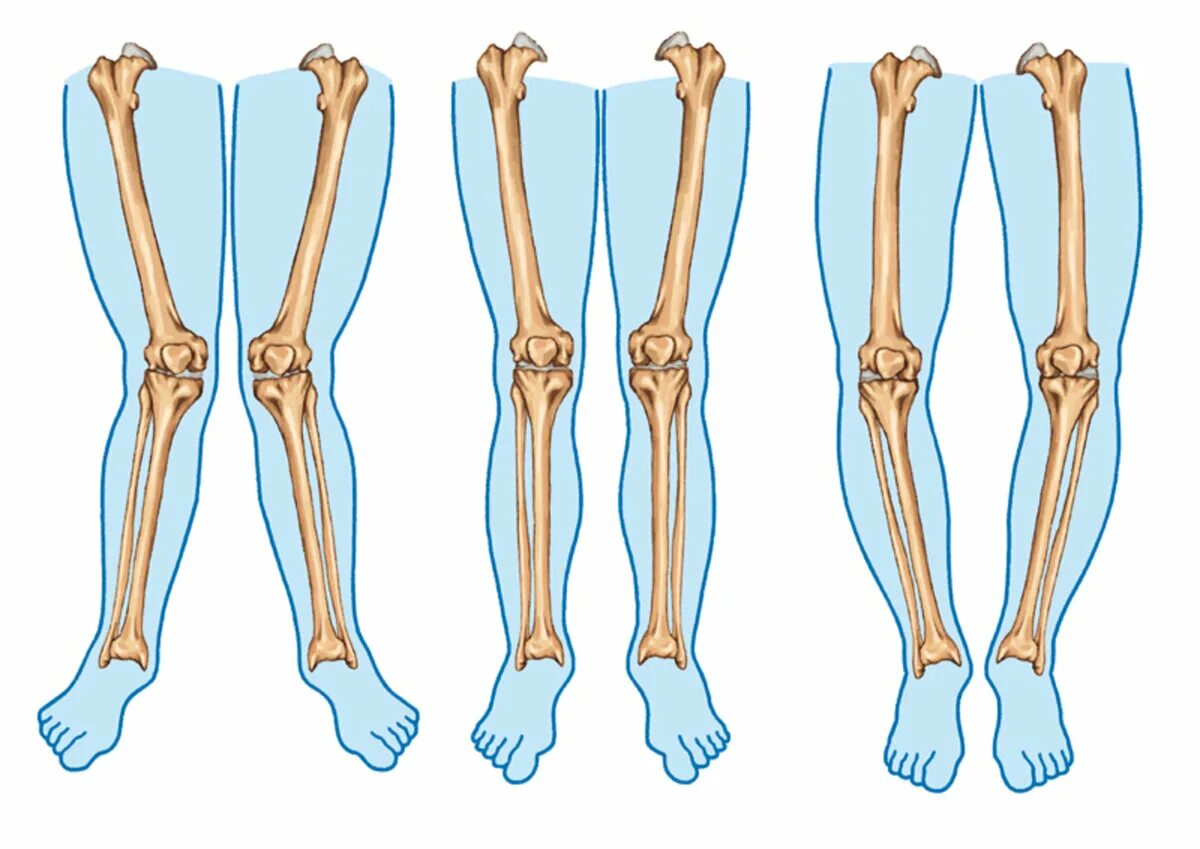

Вальгусная деформация коленных суставов у взрослых